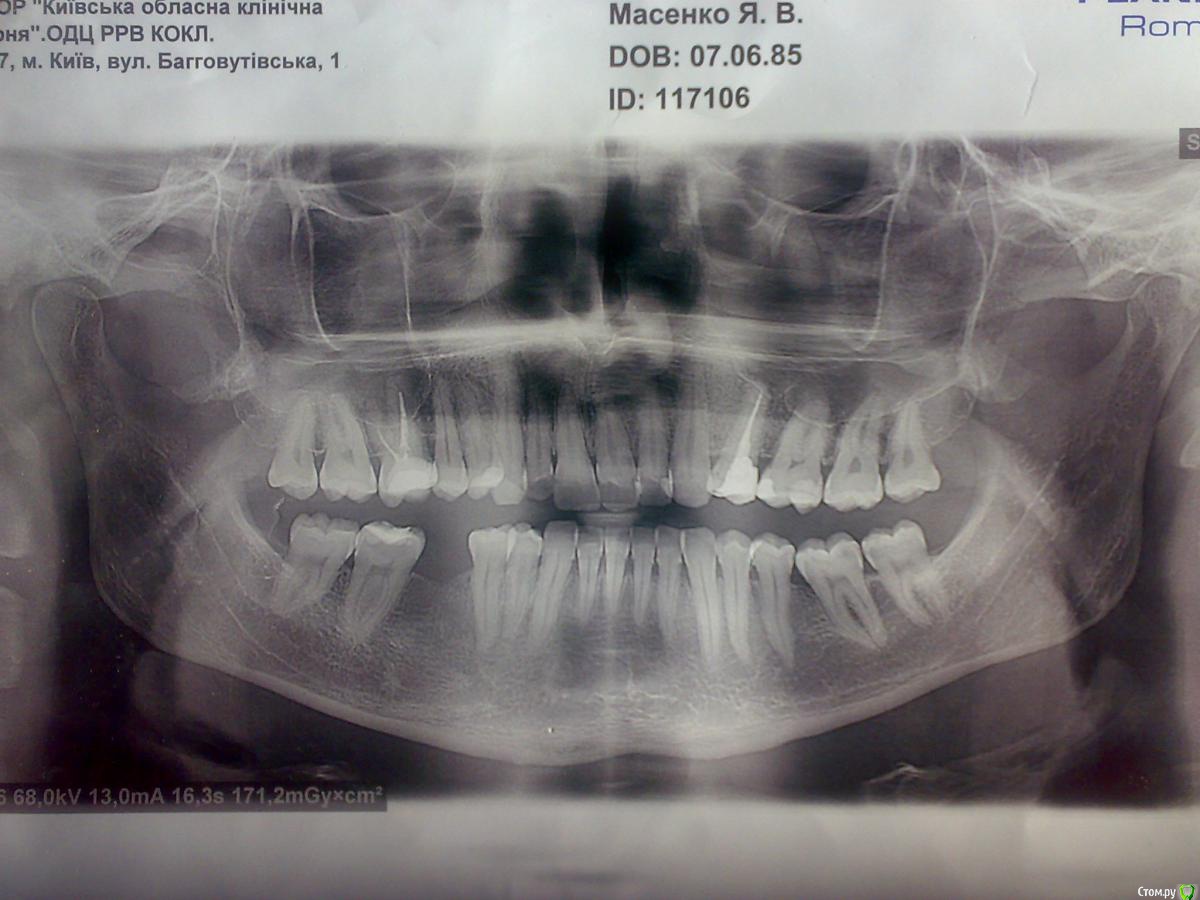

103 Опубликовано 2 апреля, 2018 Поделиться Опубликовано 2 апреля, 2018 (изменено) Прошу помощи (проблема Одонтогенного или Невростоматогенного, или может Ятрогенного происхождения...!?) Жалобы после чистки и пломбировки каналов зуба 2.5 на тянущие, жгучие боли продолжительностью вот уже почти три года где-то в в верхней челюсти слева в районе десны с нёбной стороны и в полости левой половины носа, закладывает периодически только левую ноздрю Дело было на протяжении с 2015 года по сегодняшнее времяИстория (нет, не болезни уж точно, ну да ладно таков протокол) такова, понимаю весьма долгая, но... Собственно до этого зуб не болел: обратился к врачу-стоматологу когда кариес перешёл с белого пятна в видимое поражение, а именно разрушение коронки контакта 25-го зуба со стороны 26-го .Годами ранее был удалён 24 и практически расстояние между зубами клыком и вторым премоляром сократилось до минимума.Жалко было, что 25 зуб начал разрушаться и снова портить вроде бы наладившуюся картину зубного ряда. Но ничего не поделаешь, пришлось обратится в клинику да ещё и с просьбой сохранить зуб живым, но впоследствии стоматолог счела нужным убить нерв и продолжить лечение чисткой каналов на что я до сих пор не доволен..Итак, осмотр, ну, у этой, первой длинноволосой...Врач прозондировала полость 25-го зуба ( больно не было ).Далее возникла дискуссия и прошла в таком ключе и вокруг того, что я просил у неё.Ну, и на мою просьбу сохранить зуб живым, она сказала: "Что это будет зависеть от того как она будет "проваливаться" ... По поводу того "Нельзя ли примененить прокладку?", она отвечала: "Что в моём возрасте 30 лет уже не применяется, а только детям" и т. д.Принялась искать лекарство (поинтересовавшись нет ли у меня аллергии) обошёв свой столик аж почти мне за спину ... Сделала уколы с просьбой прижать рукой в районе скулы , я удивился на интересный подход..Потом она меня спрашивала что-то ... Я говорил: "Что почему вы меня спрашивате, я пациент, вы разве не врач?" Возмущалась, что сделают что-то не сказав, потом дома ты думаешь, что да какДалее с рвением её сверления бор-машиной сменялись моими дёрганиями в кресле и её выражением: "Что дальше ещё больнее будет..." спорами по поводу того врач она или не врач... - "Как ни как, а проработала я уже 9 лет" Моим комментарием: -"Вы целенаправленно вскрываете зуб!"... Она: - "У вас тут всё уже открыто". Обзывала меня мнительным. И что если я боюсь лечиться сдесь то чтоб у другого врача тогда. Я отвечал: "Что если б я боялся, я сюда не пришел бы" При этом всё спрашивала ещё "Что действительно болит...?" - "Ну а я ведь должен же как то реагировать на Ваши манипуляции!!!"Таки в конце-концов рассверлила и наложила лекарство на нерв и наложила временную пломбу. Указала на повреждённую деснуНа этом и разошлись с этой прелестной врачихой. Ну и угораздило меня тогда к ней зайти на свою голову поставить просто пломбу.Хотя я понимаю всю серьёзность ситуации и привел это вступление так сказать ещё и потому что при общении с другим человеком с медицины у которой та же проблемма с зубом была у неё возник вопрос: "Я так и не поняла, почему вам депульпировали зуб?"Да, согласен, вопрос спорный, но как говориться ей виднее.. Следующий прием не такой описуемый по ощущениям, хотя тоже не из приятных. Зуб вроде особо не беспокоил перед приёмом, накануне видимо "упокоился" под лекарством.Вторая Стоматолог, которая чистила и лечила каналы гуттаперчевыми штифтами с лекарством, с прекрасными отзывами у больных и коллег как профессионал своего дела да ещё и моя одноклассница продемонстрировала мне снимок и сказала, что всё нормально пролечено и мне повезло,что каналы широкие и не должно быть проблем. Указала на повреждённую десну и предложила мне полоскания из трав для снятия воспаления десны....Правда в ходе манипуляций в каналах было неприятно где-то у верхушки и в конце процедуры у меня что-то потянуло или онемело в районе верхней губы и носа слева и в ходе укола с нёбной стороны было больновато. Ещё я спросил что-то на счёт не находятся ли корни в гайморовой пазухе? Одноклассница ответила, что её вообще тут на снимке не видно Потом спустя опять отведённое на это время между приёмами, третим стоматологом зуб был восстановлен пломбой со св-штифтами. После процедуры тоже было как то дискомфортно после болезненного изьятия межзубной матрицы что-то щёлкнуло и чувствовалось что десна припухла.На этом можна было б как говориться поставить точку... Так вот, впоследствии боли преобретали всё такой распирающий характер и в области проекции нёбного канала и бугра коронки появилась чувствительность при нажимании и как будто бы ощущение раны на десне при этом десна нормальная с виду.Далее боли иррадиировали в скулу при этом верхняя область щеки как будто бы жгла. Ну я подумал что постпломбировочные боли могут давать о себе так знать .Потом боли стали приодически тревожить и ставать ноющими на протяжении лета 2015 года. Были моменты с дергающими глубокими болями. Голова даже как-то побаливала ночью и спать не давала. Снова стихало. Потом опять бросало в небольшой жар в области скулы и опять проходило на время и вот уже зуб поднывает опять и начало закладывать нос ноздрю со стороны леченного зуба . C этими жалобами я всё же побывал снова у своей одноклассницы, которая хоть и заверила, что всё норм да и стесняюсь и неудобно усомнить её в этом. Но всё же... Она взглянула на зуб, который ранее был лечен ею же, постучала и сказала, что зуб не ведёт себя так если бы была проблема с зубом . Ага посмотрели снимок и тому подтверждение: говорит одноклассница по снимку проблем нет.Решила она поставить пломбу на апроксимальную поверхность зуба 2.6 на котором ранее была уже пломба с другой стороны и предложила мне полоскания из трав для снятия воспаления десны.... Я пересмотрел потом тоже структура корня сияет от белизны полоска из гуттаперчи в пределах канала корня , хотя мне периодонтальная щель показалась расширена сбоку по контуру корня между 5 и 6.И опять я спросил, что-то по поводу нёбного канала, которого не видно на прицельном снимке. Одноклассница сказала, что этот аппарат не даст такой видимости нёбного . Я подумал и сказал, значит надо КТ.... и отправился в недоумении домой. Потом после очередных мучений с болью я опять навестил свою знакомую одноклассницу-врачаЯ рассказал всю симптоматику, с жалобами, что видимо воспаление десны передаётся на слизистую оболочку Гайморовой пазухи....или нависающий край пломбы, или нерв там остался , или со штифтами всё ли нормально , или боюсь что б трещины не было, не знаю вообщем что, смотри!!!! Из её уст я услышал: "Что может быть усадка" ...Вообщем подпилила указанный мной нависающий край пломбы на 2.5.Ещё раз осмотрев полость рта и зуб, ничего такого она не увиделаРядом был коллега Стоматолог-Хирург, которого одноклассница позвала за помощью, так сказать, что бы он удостоверил меня в том же... Пристально осмотрев указанный 25 зуб и десну ничего не увидел...указав правда на проблему с дёснами, гингивит в районе передних зубов, что может оттуда отдавать.Он спросил еще по поводу снимка в одноклассницы, что нет ли там на снимке чего-то . - "Нет, ничего" последовал ответ. Я ещё возразил: "Что снимок может и не показать!" Я предположил, что инфекция с боку периодонта зуба и ... Гайморова пазуха. Может быть одонтогенный гайморит? Всё это был персонал гос. больницы в которой я ранее работал но и ещё ведущих приём в этой частной клинике по месту моего жительства (за исключением первой и третьей врача в нашей истории, приезжие) но они видимо не помнили, и каждый раз удивлялись то медсестра, то врач меня спрашивала то теперь врач-хирург медсестру и врача или у меня: - "Кто это?", - "Кто я ?", -" Врач наверное?" Хотя это и не суть важно... В общем и с этим хирургом я тоже вступил в дискуссию... Я указал на боли в области около ноздри над губой слева. Он подтвердил: "Но тогда это гайморит ..."Камнем преткновения в нашем разговоре стала анатомическая особенность расположения корней верхних зубов в Гайморовой пазухе и возможной проблеммы из-за этогоНо также был высказан им вариант как одонтогенного так и неодонтогенного гайморита. Он меня спрашивал не простужался я или не просквозило где... Нет, отвечал я . Я говорил, что речь идёт конечно про одонтогенный. Он: "Раз корни в Гайморовой пазухе, значит одонтогенный"Разошлись с рекомендациями посетить ЛОРа и сделать рентген.Уходил в конце я опять с вопросом: "Боюсь что б не было трещины.... На что может быть такая реакция?" А в ответ - тишина... Следующий визит был у ЛОРа местной поликлиники где также я рассказал вышеуказаные жалобы с предполагаемым диагнозом. ЛОР-врач осмотрел и предложил сделать рентген-снимок придаточных пазух носа.Я сделал и пришёл к ниму сказав, что не знаю что вы тут увидите. И в правду он спросил: "С какой стороны у вас проблема?" Я говорю слева . Ага, рассмотрев рентген-снимок сказал, что с левой стороны не чёткий контур в районе зубов и Гайморовой пазухи и предложил выписать направление в Областную больницу: "Пусть вас там посмотрят, поскольку тут случай на грани стоматологии и лор..."Диагноз Одонтогенный гайморит слева под вопросом Далее был уже в Киеве в Областной больнице на приёме у ЛОРа, который на основании осмотра с моих жалоб и по тому же снимку тоже точно не мог определить есть ли там гайморит или нет и отправил к своему коллеге Зав. отд. КМН, моему тёзке, который одним росчерком пера направляет на Рен. КТ ППН. В следующий визит было проведено КТ. Рассмотрев снимок и описание КТ осмотреть меня принялась уже зрелая барышня, тоже ЛОР (сославшись на то "...Что я не доверяю тому, что там написано, а посему я вас сама осмотрю.") Прозвучал следующий вердикт: "Вы не ЛОР-больной!"... Вам надо пролечить тройничный нерв. Ну, подумал, значит к невропатологу... Записала в карточку свой диагноз Вторичная невралгия V парыЯ что-то пытался ей возразить в одном моменте, на счёт возможного отёка, как было записано в расшифровке КТ, но последовал суровый взгляд и слово "нет", а также "Если б всё так просто было!?" , и пошло-поехало вот "Читайте..." и в голос перечитывает мне описание КТ... Я только молча слушаю "у матросов нет вопросов"... Выписала Лоратадин Направился, взяв в охапку разные мед. бумаги, рентгеновские плёнки, к врачу-Неврологу по фамилии Беда...Та даже не взглянув на те самые снимки, но браво начала проводить свои тесты, умыв свои ручки в умывальнике и резво заявила на мои жалобы и то, что вот уже проведены нужные осмотры и обследования: "Ага, ну да вот пусть и разбираются Стоматологи с ЛОРами: лечат ваши каки-ето хронические заболевания... Значит что-то давит там на нерв..." и в таком духе... Прописала мне принимать Лирику Круг замкнулся. Пошёл я опять в Стоматологию, но уже, правда, как я говорил, здесь же, это областная больница отделение ЧЛХ. Дело было под конец рабочего дня и я с моими родственниками, пересекаюсь на горизонте, как оказалось потом с обходительным Хирургом этого отделения, который прочитав заключение Невролога о дообследовании у ЛОРа и стоматолога,предложил свой осмотр. Осмотрев и выслушав внимательно мою историю с целью дообследования назначил ОПТГ, что вы можете видеть здесь., на которой впоследствии тоже не было выявлено хир.патологии и снимок КТ он тоже посмотрел, ничего не сказав. Предложил посетить стоматолога. Итак, направляюсь к стоматологу и тут же по коридору оборачиваясь на возглас из-за своей спины: "Что у вас там, гайморит? Давайте снимочек" встречаю её самую Стоматолога. Пригласив меня в свои аппартаменты, уложила в кресло и начала осматривать и снимок, на котором она не видит того самого гайморита и меня, сделав замечание по поводу плохого ухода за зубами и начали мы разбираться по поводу того что может быть с этим зубом, спрашивая меня то я её о проведённом лечении, вопросов к которому у неё нет по ОПТГ. Читала запись постановки диагноза Воспаления тройничного нерва и была возмущена. Сказала, что по ОПТГ только видит Генерализированный пародонтит I-II ст., хр. течение, ст. обострения. В итоге что б не думать и гадать предложила она сделать ещё дентальную 3D компьютерную томограмму верхней челюсти отдельного сегмента 25,26,27 зубов направив в какую-то городскую клинику где её делают, потом с лично её последующей расшифровкой и приёмом в скором будущем по записи, поскольку день рабочий уже заканчивался и я приехал в столицу за 100 км. Впоследсвии позже архив записанного диска с проведённой 3D КТ я переслал ей по электронке, предварительно связавшись с ней. Но так ответа и не получил видимо там тоже ничего не прояснилось.Вот жду опять ответа от вас уважаемые Доктора как быть и что предпринимать в такой ситуации ?Прям таки дилемма: "Medice, cura te ipsum" Изменено 2 апреля, 2018 пользователем 103 Ссылка на комментарий

103 Опубликовано 8 июля, 2018 Автор Поделиться Опубликовано 8 июля, 2018 (изменено) Коллеги, что нет никаких предположений? Кроме того удалённого сообщения, что было приглашением на участие в какой-то программе где рассматривали проблему воспаления тройничного нерва...?? Снимок и КТ делались спустя Вот, ещё КТ, посмотрите, пожалуйста, сами: https://drive.google.com/open?id=1QO7cWSY9mTW80quu88hPcZqwKNRHgAZx Изменено 8 июля, 2018 пользователем 103 Ссылка на комментарий